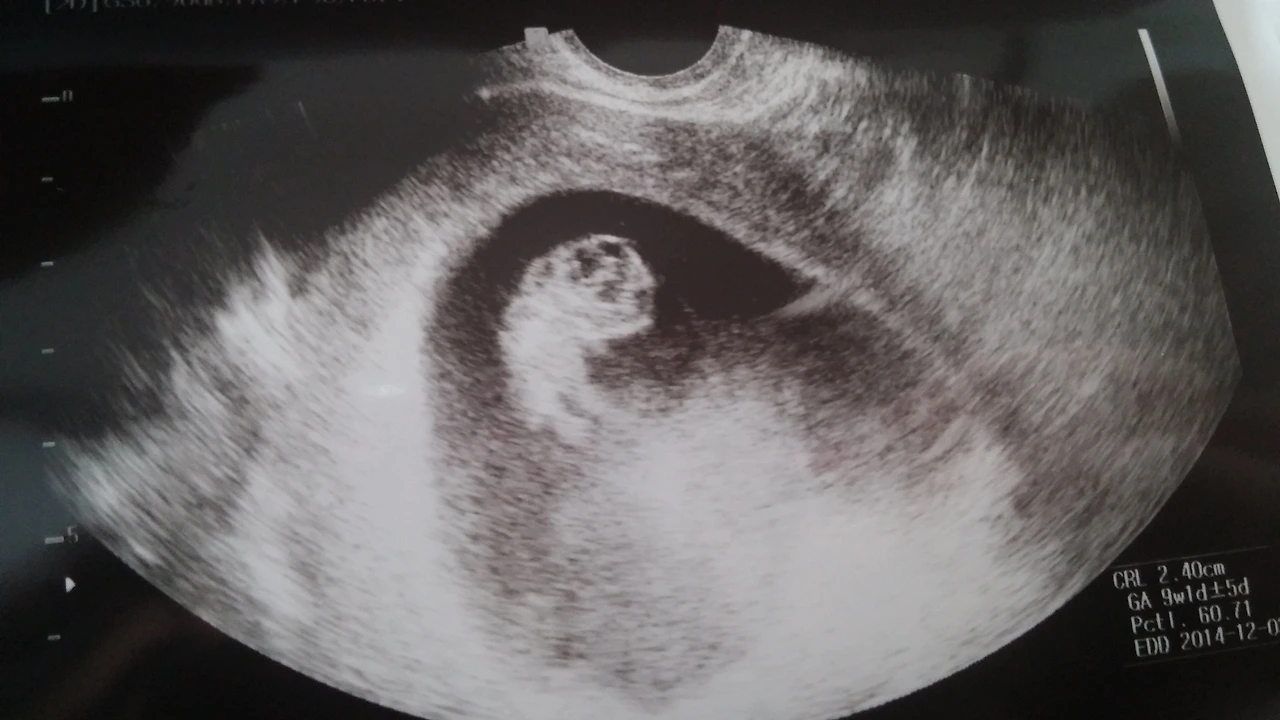

9주 + 1

12주까지는 조심 또 조심해야 한다고 하도 얘길 들어서 노심초사 돌다리도 두드려 건너는 심정으로 지냈다. 2주마다 병원 진료를 받다 보니 두렵기만 하던 산부인과 방문도 익숙해져 갔다. 12주가 지나고 안정기에 들어서면서 병원 진료는 4주에 한번, 30주부터는 2주에 한번, 36주부터는 일주일에 한번으로 바뀐다.

2주마다 조금씩 자라 있는 콩알이를 만나는 일은 매우 설레었다. 작은 녀석이 주는 인체의 신비란 놀라움의 연속이었다. 4주마다 콩알이를 만나면서는 걱정이 늘어났다. 병원에 가지 않고서는 (태동이 있기 전까지) 콩알이의 존재를 느낄 수 없었기에, 이 녀석이 과연 잘 지내고 있는 걸까? 혹시 뭔가 잘못 먹어서 아기한테 안 좋은 영향을 미치면 어쩌지? 하며 사서 걱정을 하는 여자였다.